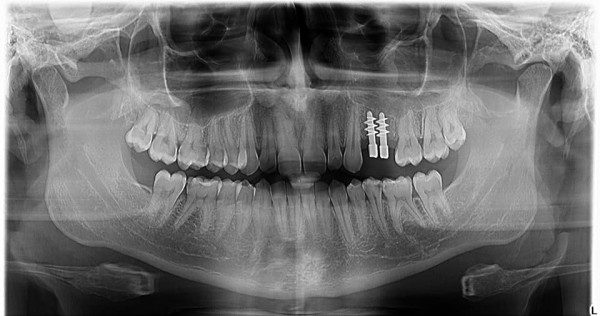

Încă de la absolvirea facultății, în anul 1994, doamna doctor Mihaela Teodorescu s-a preocupat în permanență de continuarea pregătirii profesionale, participând la numeroase congrese și cursuri de perfecționare atât în țară, cât și în străinătate, axate în special pe domeniul Implantologiei Dentare.